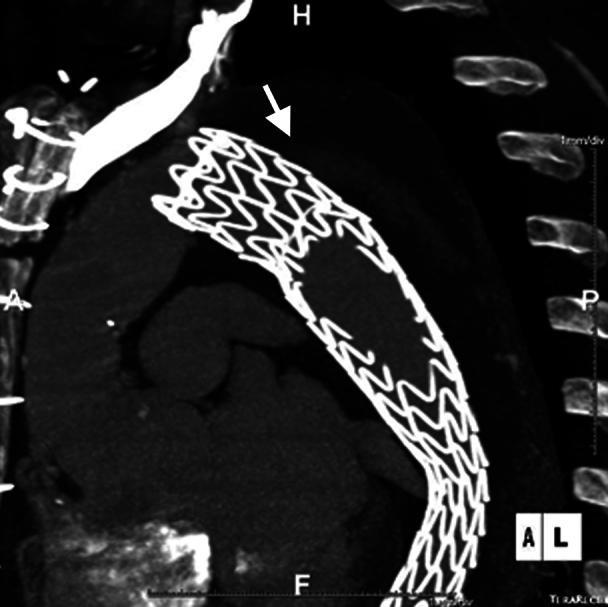

A 62-year-old man underwent an elephant trunk procedure followed by thoracic endovascular aortic repair (TEVAR). Computed tomography angiography-based models were built to quantify volume of the whole aorta and true and false lumens preoperatively, before TEVAR, after TEVAR, and at follow-up at 3, 6, and 12 months. With TEVAR, descending aortic true lumen volume increased by 54%, then increased additionally by 60% during 12 months. The descending aortic false lumen volume regressed continuously for 12 months following TEVAR, with the most rapid rate from 6 to 12 months at 16 cm/month. TEVAR immediately increased true lumen volume and continued to remodel the true and false lumens throughout the following 12 months.

一名62岁男性接受了象鼻手术,随后进行了胸主动脉腔内修复术(TEVAR)。基于计算机断层扫描血管造影术建立模型,以术前、TEVAR术前、TEVAR术后以及3个月、6个月和12个月随访时对整个主动脉以及真腔和假腔的容积进行量化。通过TEVAR,降主动脉真腔容积增加了54%,然后在12个月内又额外增加了60%。TEVAR术后,降主动脉假腔容积在12个月内持续缩小,在6至12个月时缩小速度最快,为每月16厘米。TEVAR立即增加了真腔容积,并在接下来的12个月内持续重塑真腔和假腔。